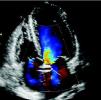

A 67-year-old woman with a history of scleroderma and hypertension but with no previous cardiac symptoms was hospitalized for assessment of systemic sclerosis. Physical examination revealed a grade II/VI systolic murmur on the apex; the electrocardiogram showed sinus rhythm and left anterior bundle branch block. Left parasternal long-axis echocardiography revealed an anomalous tubular image in continuity with the anterior wall of the ascending aorta (Fig. 1), while in parasternal short-axis view the same tubular structure was seen encircling the aorta (Fig. 2). In apical 4-chamber view, a tubular image, 2 mm in diameter and 42 mm in length, was observed crossing the atrial septum; its origin and end were not identified. Color Doppler echocardiography showed flow in its interior (Figs. 3 and 4), which raised the suspicion that it was a vascular structure, and cardiac catheterization was accordingly performed, which revealed anomalous origin of the left coronary artery (LCA) from the proximal segment of the right coronary artery, with an epicardial course anterior to the aorta (Fig. 5). The echocardiographic findings, most often associated with scleroderma, are pulmonary hypertension and pericardial involvement, including fibrinous pericarditis. There are no reports in the literature of an association between scleroderma and anomalous coronary artery origin, and hence this case may be simply a coincidence. Origin of the LCA from the right coronary ostium is found in only 0.15%1 of the population and is associated with sudden death.2